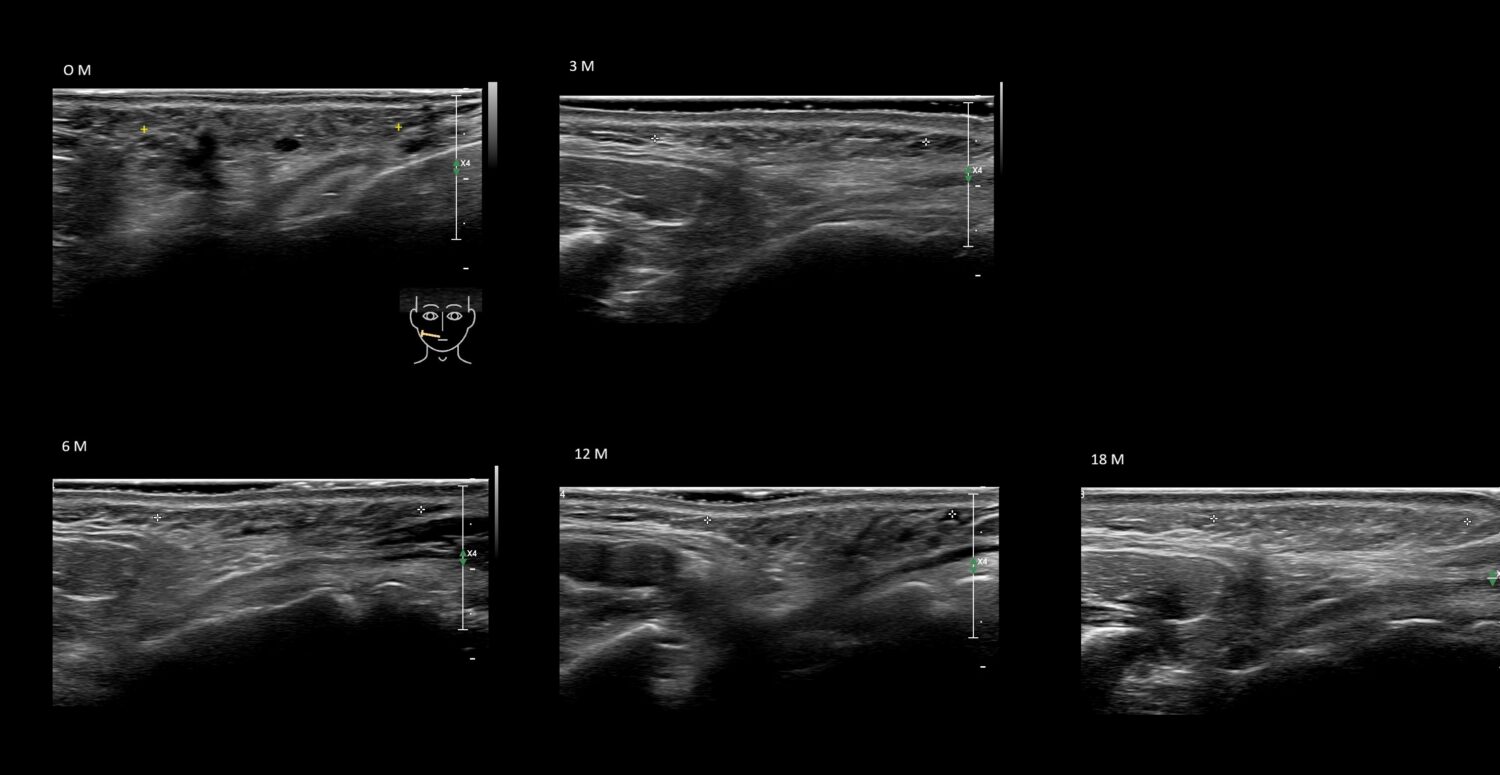

PCL 0

PCL 1a

PCL 2a

PCL 3b e

PCL 4a

PCL 4b e

PCL 5a

PCL 5b e

PCL 6a